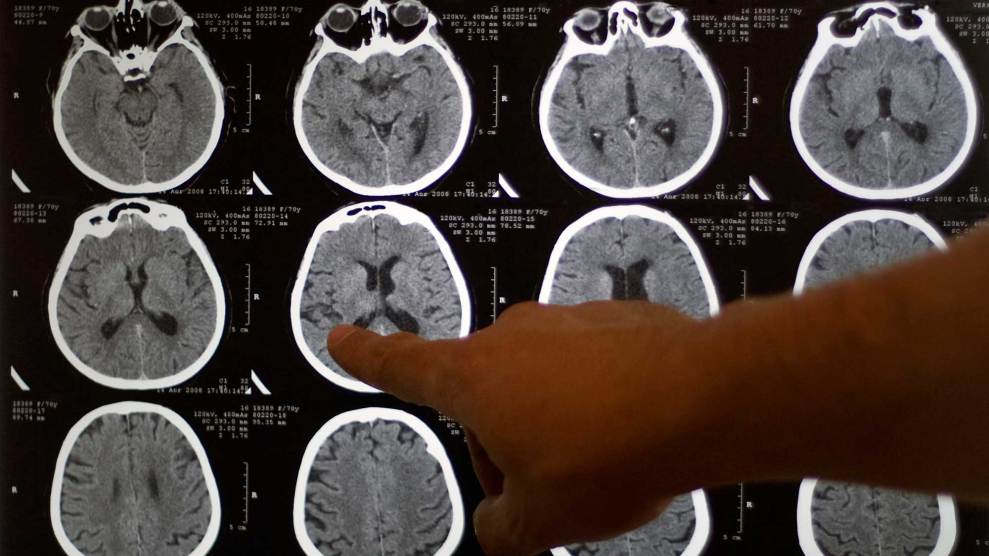

The results, which Noble and Farah reported in a 2005 paper, were the beginning of what they call a “neurocognitive profile” of socioeconomic status and the developing brain. Farah, Noble, and other scientists soon began using magnetic resonance imaging (MRI) scans to examine the brains of children across the socioeconomic spectrum. The results were striking. In one study Farah looked at 283 MRIs and found that kids from poorer, less-educated families tended to have thinner subregions of the prefrontal cortex—a part of the brain strongly associated with executive functioning—than better-off kids. That could explain weaker academic achievement and even lower IQs.

In 2015, Noble co-authored the largest study to date. Using MRI, researchers examined 1,099 children and young adults and found that the brains of those with higher family income and more parental education had larger surface areas than their poorer, less-educated peers. The strongest correlation came in brain regions associated with language and executive functioning. What’s more, the data indicated that small increases in family income had a much larger impact on the brains of the poorest children than similar increases among wealthier children. And Noble’s data also suggested that when a family falls below a certain basic level of income, brain growth drops off precipitously. Children from families making less than $25,000 suffered the most, with 6 percent less brain surface area than peers in families making $150,000 or more.

A few months later, another large study co-authored by Seth Pollak, a child psychologist at the University of Wisconsin-Madison, found strong ties between household income and the volume of gray matter in the frontal lobe, temporal lobe, and hippocampus. Children from households below the federal poverty line ($24,250 for a family of four in 2015) had 8 to 10 percent less gray matter in these critical regions. And even kids whose families were slightly better off—incomes of one and a half times the federal poverty level—had 3 to 4 percent less gray matter than the developmental norm. In Pollak’s study, many of the poor parents were highly educated, indicating that the “maturational lags” their children suffered from were a direct result of the circumstances of poverty.